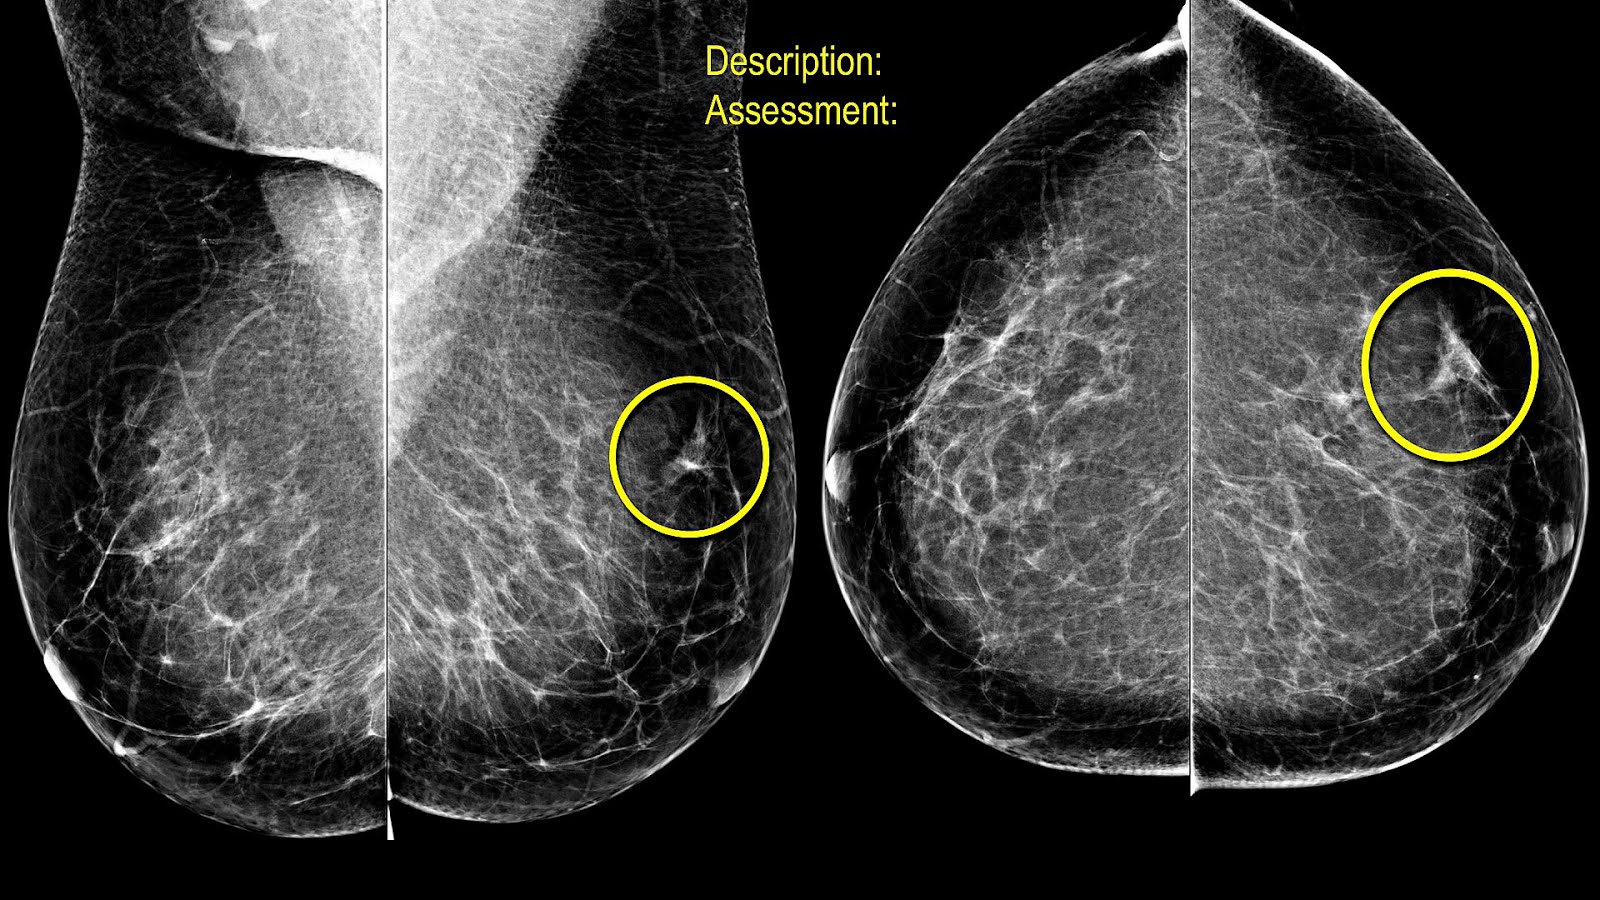

La mastografía es el estudio de imagen más utilizado para la detección temprana del cáncer de mama. Sin embargo, a lo largo del tiempo han surgido diversos mitos en torno a su efectividad, seguridad y utilidad en la prevención de enfermedades mamarias. Es fundamental conocer la información basada en evidencia científica para desmentir creencias erróneas y fomentar la detección oportuna.

La mastografía es el estudio de imagen más utilizado para la detección temprana del cáncer de mama. Sin embargo, a lo largo del tiempo han surgido diversos mitos en torno a su efectividad, seguridad y utilidad en la prevención de enfermedades mamarias. Es fundamental conocer la información basada en evidencia científica para desmentir creencias erróneas y fomentar la detección oportuna. La tomografía computarizada (TC) es una de las herramientas más avanzadas y eficaces utilizadas en la medicina para obtener imágenes detalladas del interior del cuerpo humano. A través del uso de rayos X y procesamiento computarizado, esta técnica permite a los médicos diagnosticar una amplia variedad de enfermedades y condiciones. Sin embargo, como con cualquier procedimiento médico, es natural que los pacientes tengan preguntas sobre el examen. Este artículo aborda las preguntas más frecuentes sobre la tomografía computarizada, ofreciendo información clara y precisa.